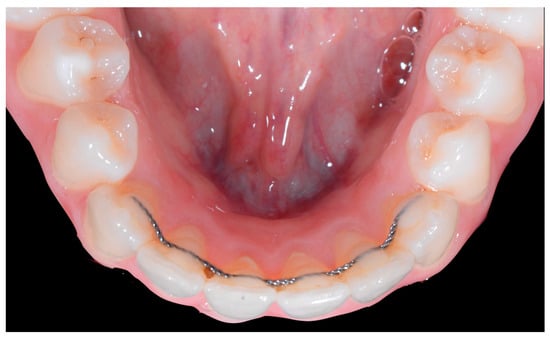

The occlusal views provide additional relevant information (Figure 9 and Figure 10). A maxillary retainer was present on 11 and 21 only and a difference in visibility of the vestibular surfaces (differential torque) on these same teeth was noted.

Figure 9.

Intermediate wire syndrome. Occlusal view.

Figure 10.

In the mandible, the retainer was broken distal to 42 and, despite being intact on 33, this tooth had increased visibility of its vestibular surface compared to its contralateral tooth (differential torque). Finally, teeth 31 and 41 also showed a difference in the visibility of their vestibular surfaces (differential torque). Ultimately, the patient was diagnosed with an X-effect wire syndrome on 21, an X-effect wire syndrome on 41, and a Twist-effect wire syndrome on 33.